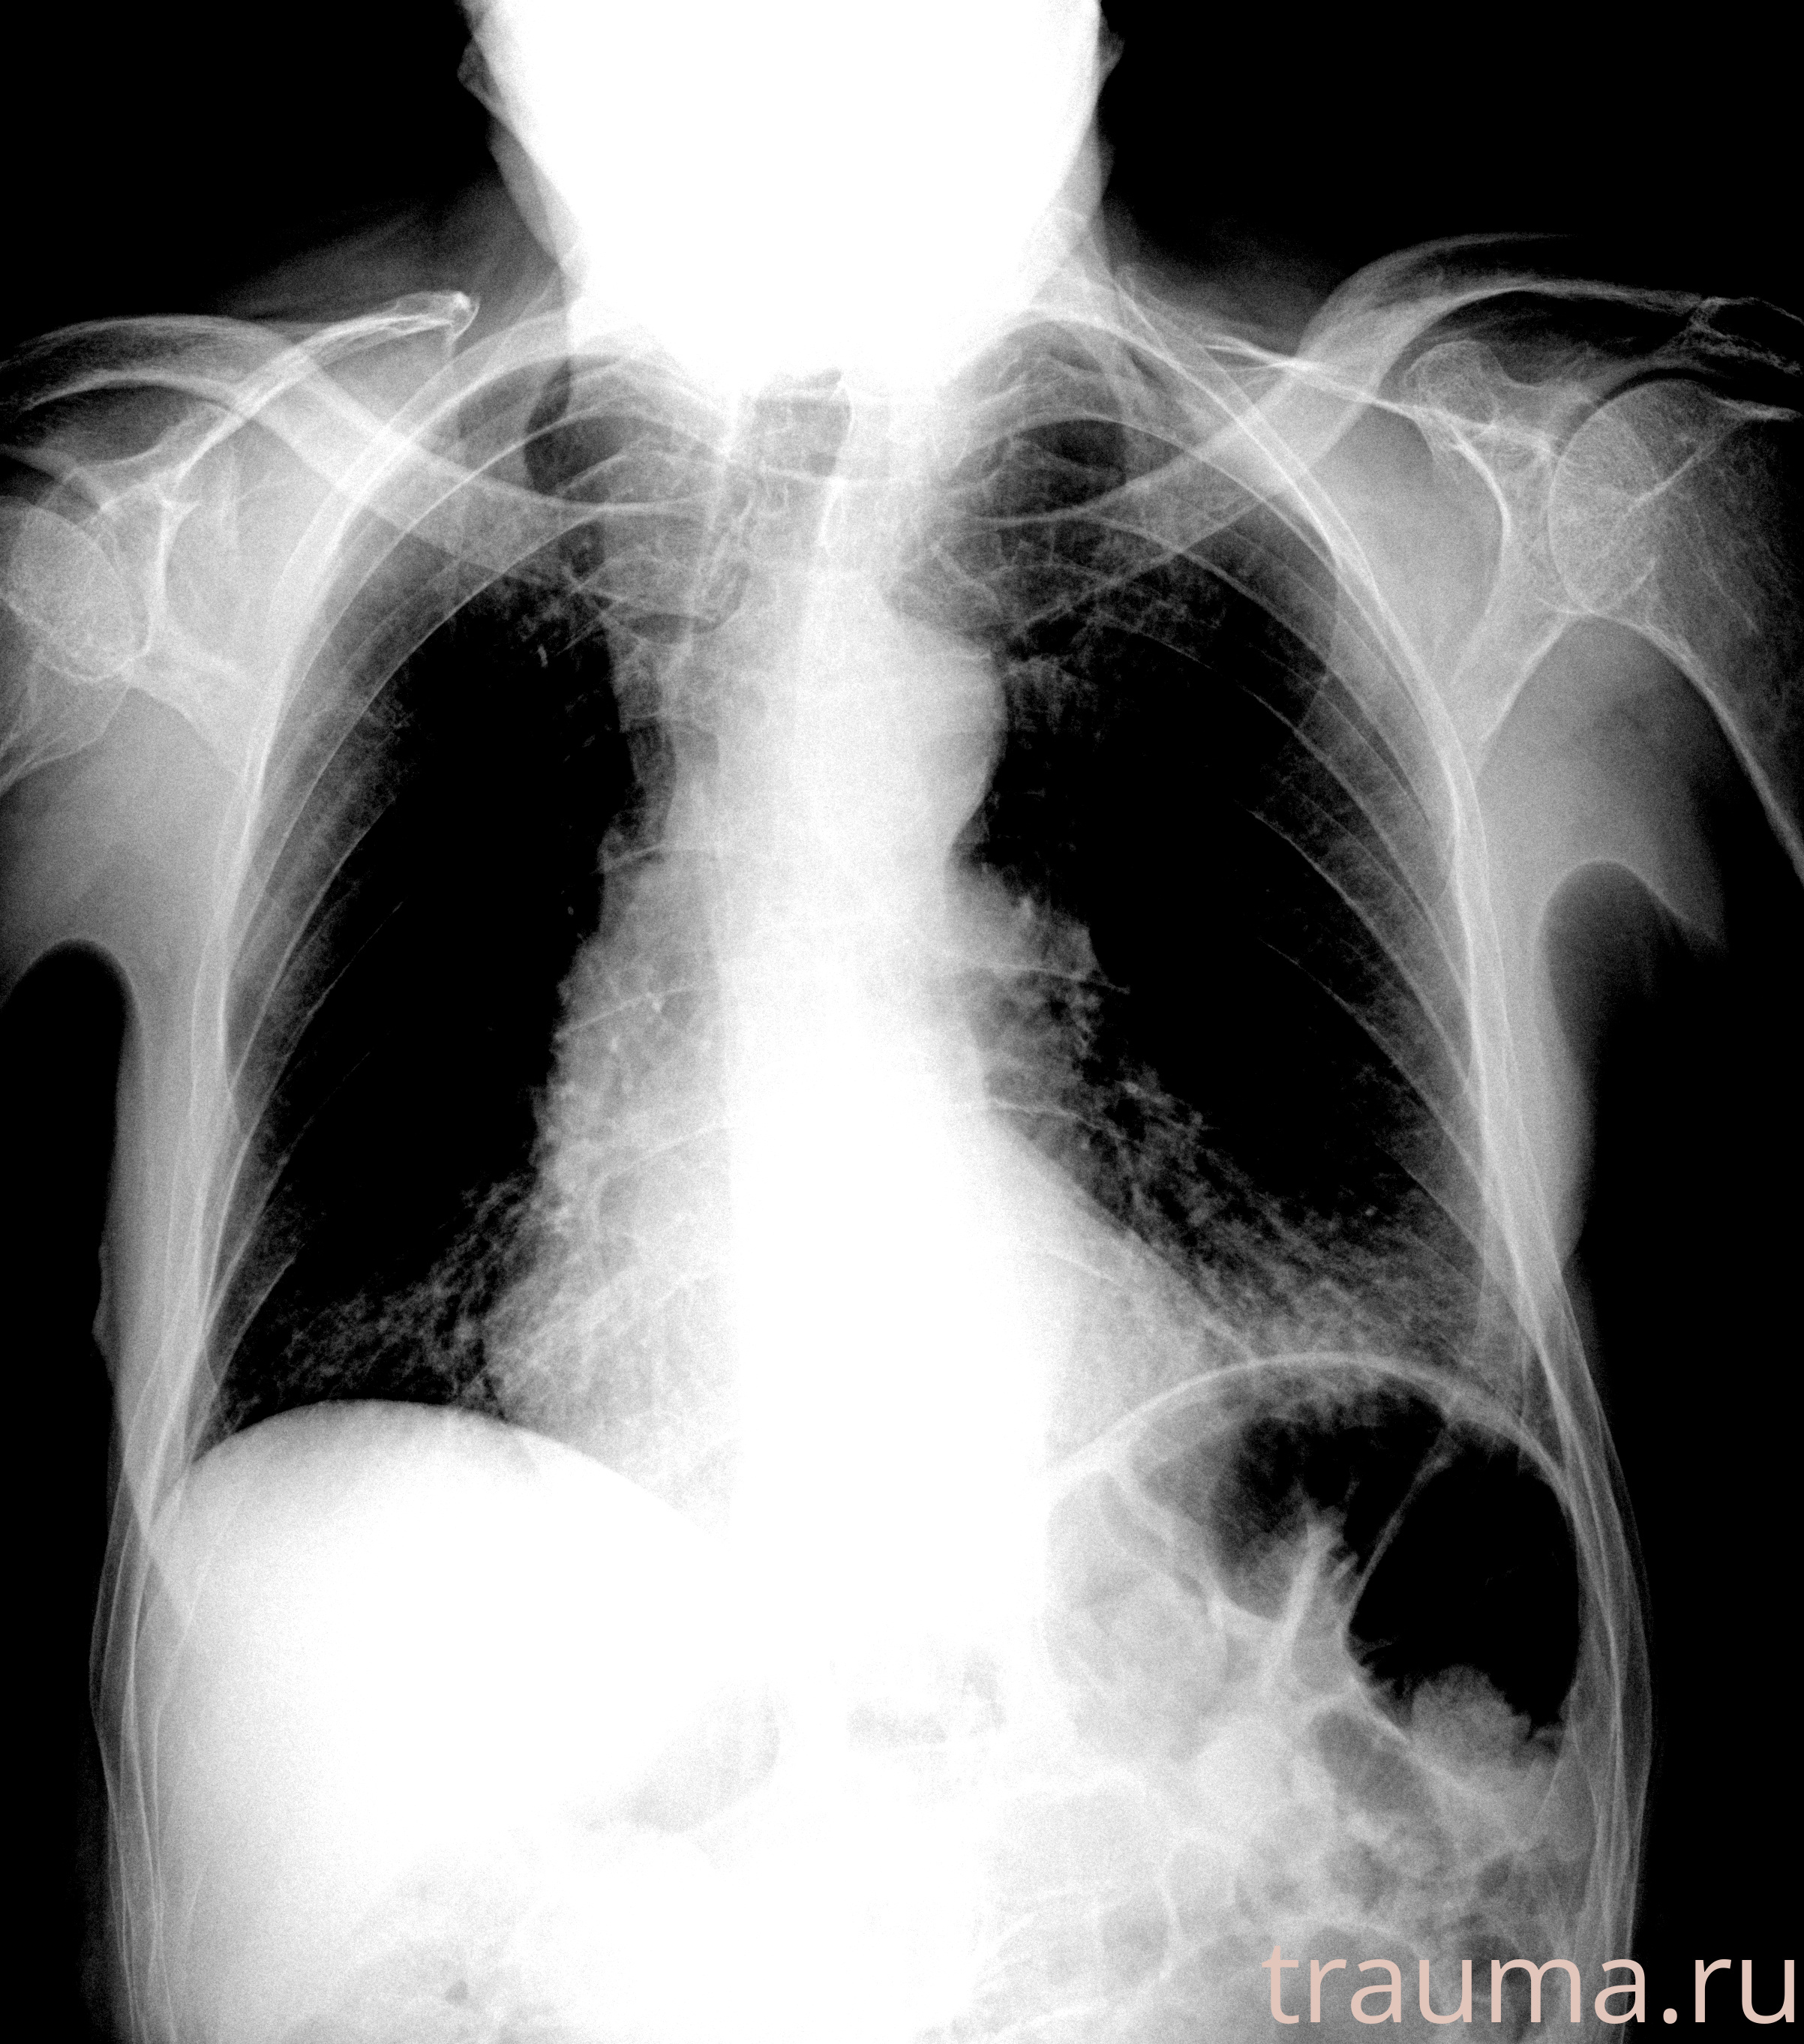

Рентгенограммы

Рентген на дому: по вашему адресу приезжает врач-рентгенолог, травматолог-ортопед с мобильным рентгеновским аппаратом, проводит диагностику травмы или заболевания, делает необходимые рентгенограммы, дает рекомендации по дальнейшему лечению. Получить качественные снимки в домашних условиях возможно благодаря уникальной методике, разработанной МосРентген Центром для института  Склифосовского